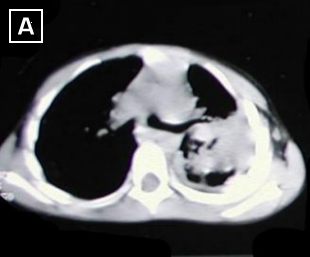

Rx. Tórax PA. (A). posterior a la insercion del tubo de tórax para drenaje pleural. radiopacidad difusa del hemitórax izquierdo, con colapso parcial pulmonar, desviación mediastinal hacia la derecha. Por proceso neumonico con derrame pleural.

Cortes tomograficos A - B - C - D : Desde carina hacia base del tórax, dezplazamiento de la carina a la derecha, severo engrosamiento pleural izquierdo, con tabicamiento, disminucion del volumen del hemitorax izquierdo, además reporta areas de atelectasia pulmonar en lóbulo inferior izquierdo.